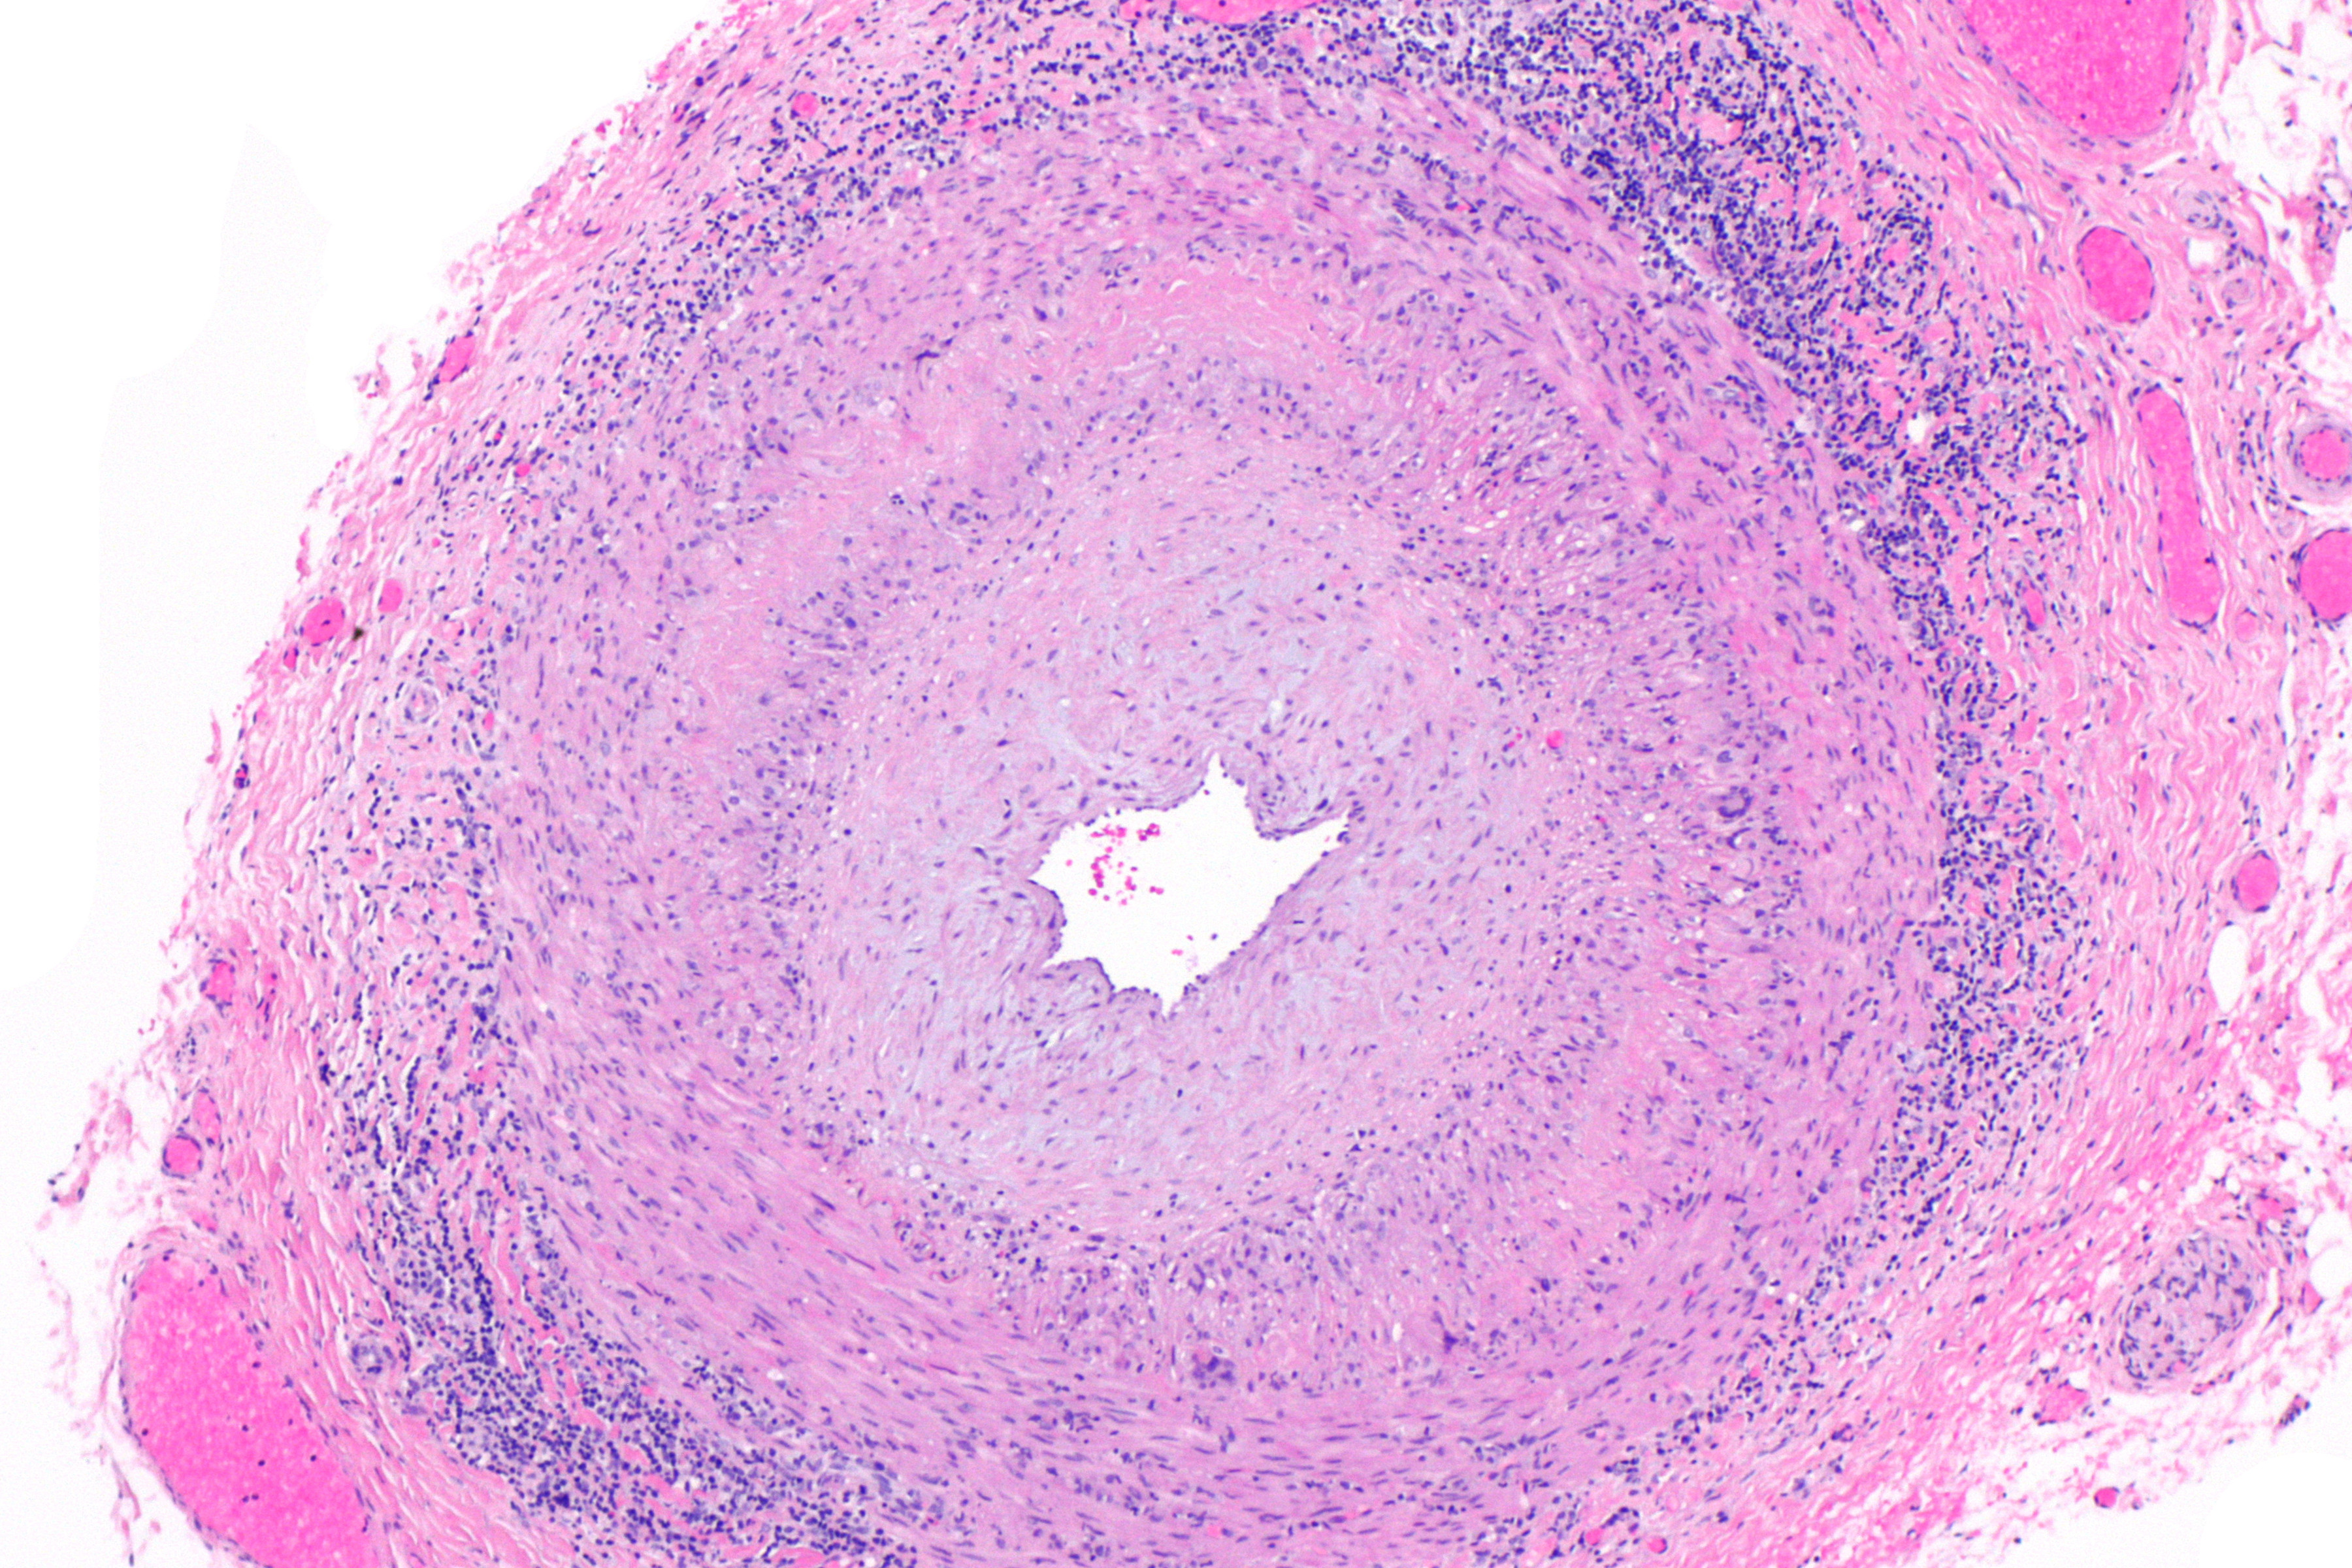

![Arteriitis temporalis (click on photo to enlarge) [source: Opzwartbeek - Wikimedia - Creative Commons License 4.0] Arteriitis temporalis](../../../images/arteritis-temporalis-1z.jpg) |

![Arteriitis temporalis (click on photo to enlarge) [source: Nephron - Wikimedia - Creative Commons License 3.0] Arteriitis temporalis](../../../images/arteritis-temporalis-2z.jpg) |

Foto's:

Opzwartbeek en Nephron - Wikimedia (Creative Commons License

3.0).